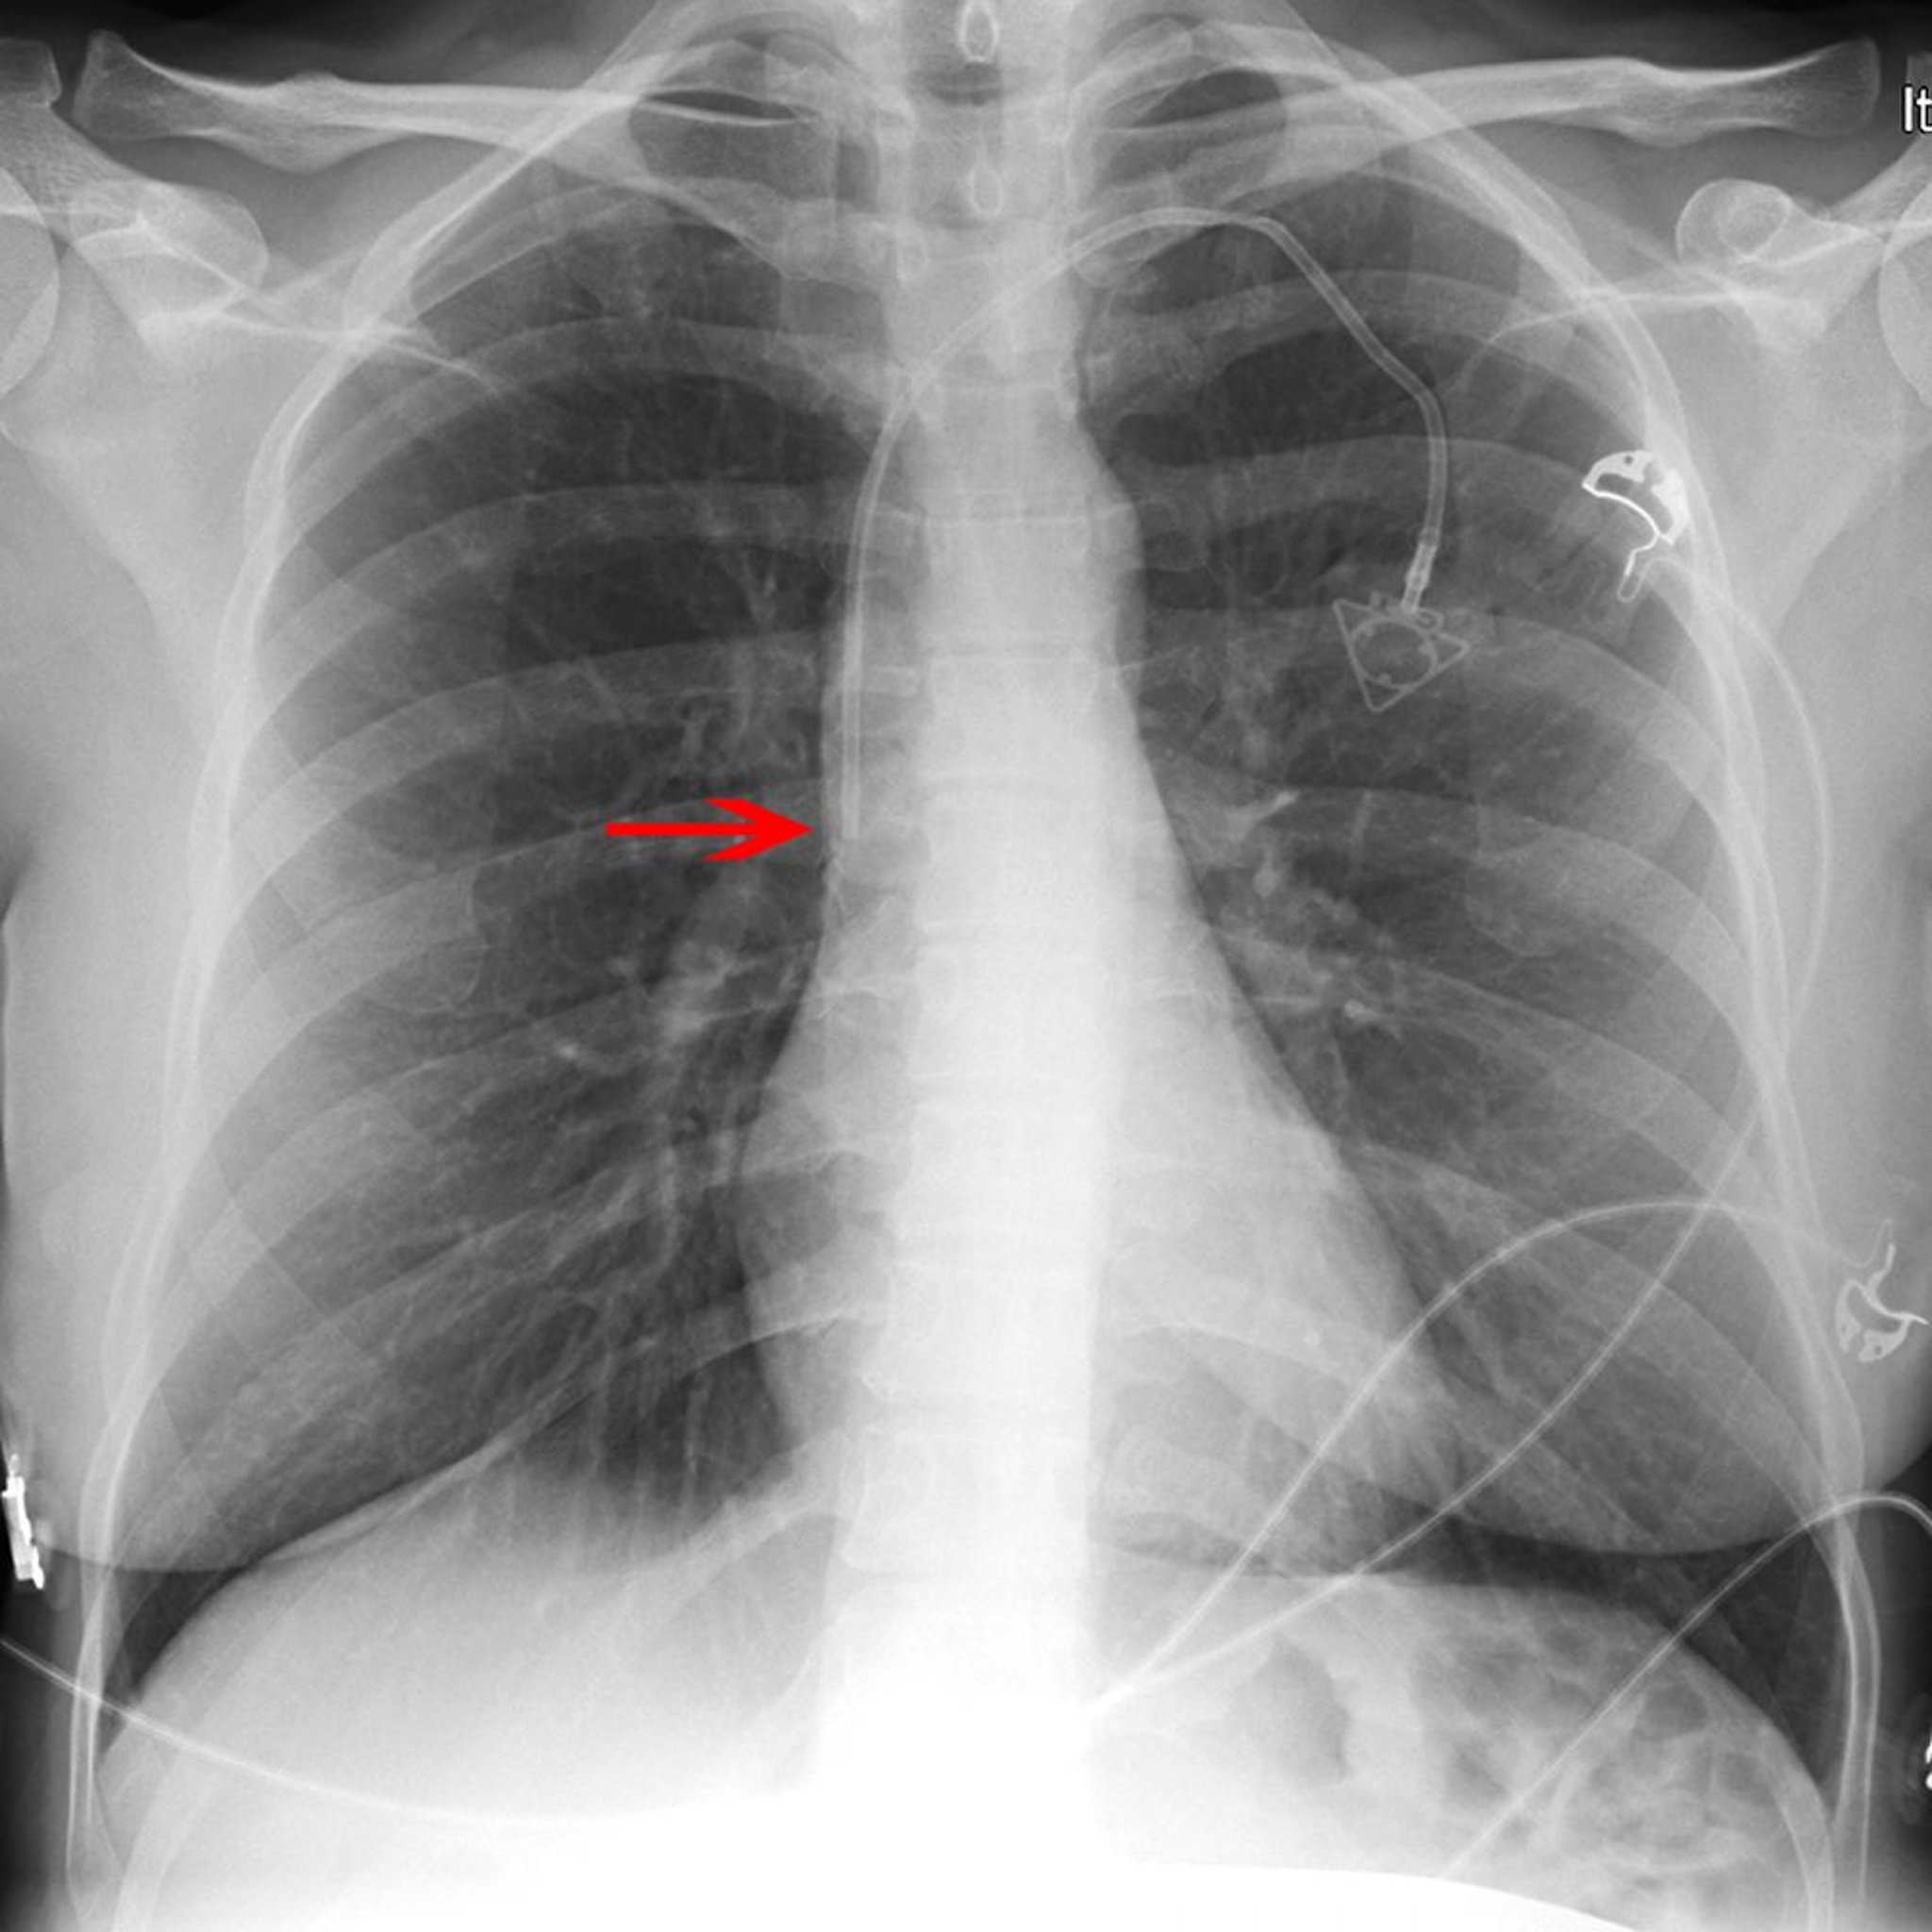

Radiografía de un catéter venoso central

La flecha roja señala la punta de un catéter en la vena subclavia izquierda (colocado apropiadamente en la porción inferior de la vena cava superior).

© 2017 Elliot K. Fishman, MD.